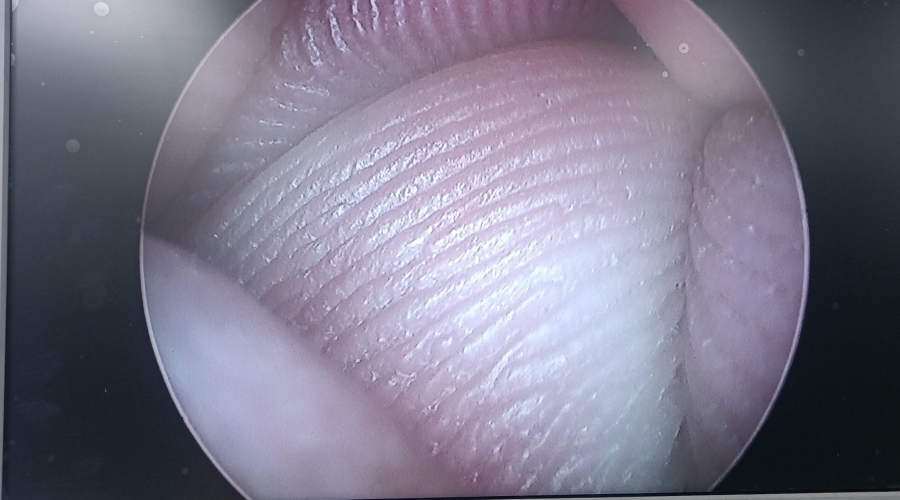

故障內(nèi)容圖像模糊,棒透鏡破碎,導(dǎo)光錐破碎,目鏡罩破碎,鏡身有磕碰,但不影響使用。

維修方案更換棒透鏡、導(dǎo)光錐、目鏡罩,校對圖像,內(nèi)窺鏡抗震蕩抗沖擊性能測試,內(nèi)窺鏡密封性性能檢測;內(nèi)窺鏡抗震蕩性能測試,內(nèi)窺鏡冷熱沖擊性能檢測。